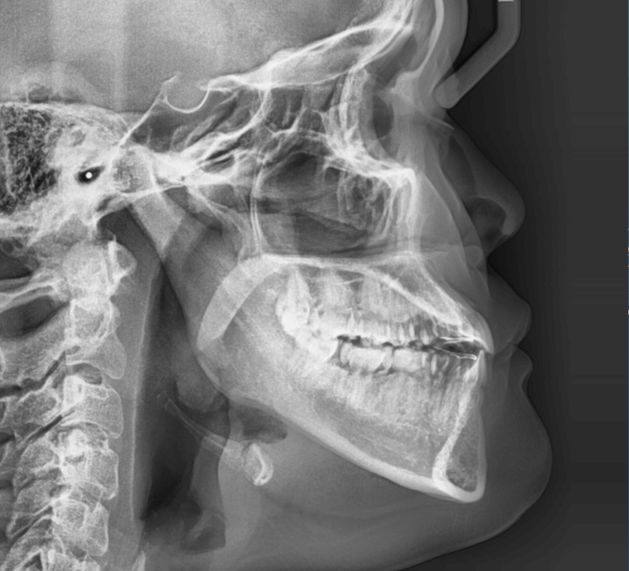

| 年齢・性別 | 15歳の女性 |

|---|---|

| 主訴 | 咬み合わせが逆であること(反対咬合)を気にされて来院された15歳7か月の女性。見た目や機能面の改善を希望されていました。 |

| 治療期間・回数 | 4年4ヶ月・28回 |

| 費用 | 900,000円 |